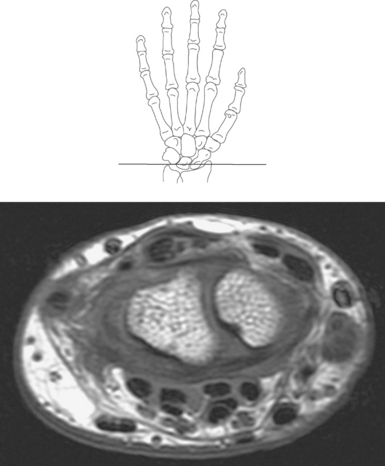

Numerous ligaments provide additional stability to the wrist. The extrinsic ligaments reinforce the joint cavity surrounding the carpal region and include palmar and dorsal radial carpal ligaments, the radial and ulnar collateral ligaments, and the TFCC (Figures 9.115 through 9.117). The many articulations between the carpal bones are supported by the intercarpal ligaments or intrinsic ligaments that connect the carpal bones to each other (Figure 9.115). The configuration of the intrinsic ligaments, metacarpal ligaments, and triangular fibrocartilage complex creates five different joint compartments that can be demonstrated at arthrography: (1) compartment of the first carpometacarpal articulation, (2) common carpometacarpal compartment, (3) mediocarpal compartment, (4) intermetacarpal compartment, and (5) radiocarpal compartment (Figure 9.115). The carpal tunnel is created by the concave arrangement of the carpal bones (Figure 9.103). A thick ligamentous band called the flexor retinaculum (transverse carpal ligament) stretches across the carpal tunnel to create an enclosure for the passage of tendons and the median nerve (Figures 9.118 through 9.120). The flexor retinaculum inserts medially on the pisiform and hook of the hamate and spans the wrist to insert laterally on the scaphoid and trapezium. In addition to the carpal tunnel, another tunnel called Guyon’s canal is formed where the ulnar extension of the flexor retinaculum continues over the pisiform and hamate. This creates a potential site for compression of the ulnar nerve (Figures 9.118, top, and 9.119). The extensor retinaculum (dorsal carpal ligament), located dorsally, is much thinner. It attaches medially to the ulnar styloid process, triquetrum, and pisiform and laterally to the lateral margin of the radius (Figure 9.120, left). Along its course it forms six fibroosseous tunnels for the passage of the synovial sheaths containing the extensor tendons (Figure 9.118, bottom).

The numerous muscles of the forearm become tendinous just before the wrist joint. The many tendons located in the wrist can be divided into palmar and dorsal tendon groups (Figures 9.120, A and B and 9.127). The palmar tendon group collectively flexes the fingers and wrist. As this group courses through the carpal tunnel, the tendons appear to be arranged in two discrete rows (Figures 9.118, A and 9.119). The tendons of the dorsal tendon group, spanning the superficial surface of the wrist, are considered the extensors of the fingers and wrist (Figures 9.128 through 9.140).